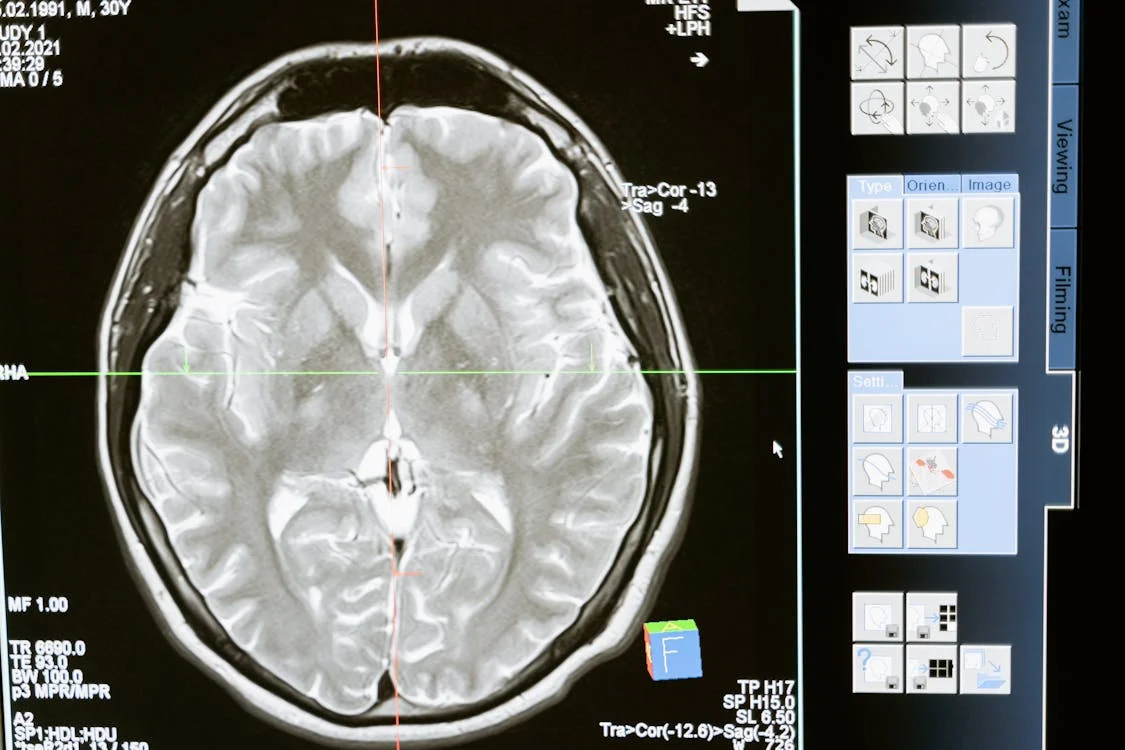

치매는 단순한 기억력 저하가 아니라, 인지 기능이 점차 저하되면서 일상생활 수행이 어려워지는 질환입니다. 일반적으로 65세 이상에서 많이 발생하지만, 젊은 사람들도 걸릴 수 있습니다.

• 알츠하이머병: 전체 치매 환자의 60~70%를 차지하며, 베타아밀로이드 단백질이 뇌에 쌓이면서 뇌세포를 파괴합니다.

뇌졸중(뇌경색, 뇌출혈)으로 인해 뇌세포가 손상되면서 발생하는 치매입니다. 고혈압, 당뇨, 고지혈증 등의 질환이 있으면 위험이 증가합니다.